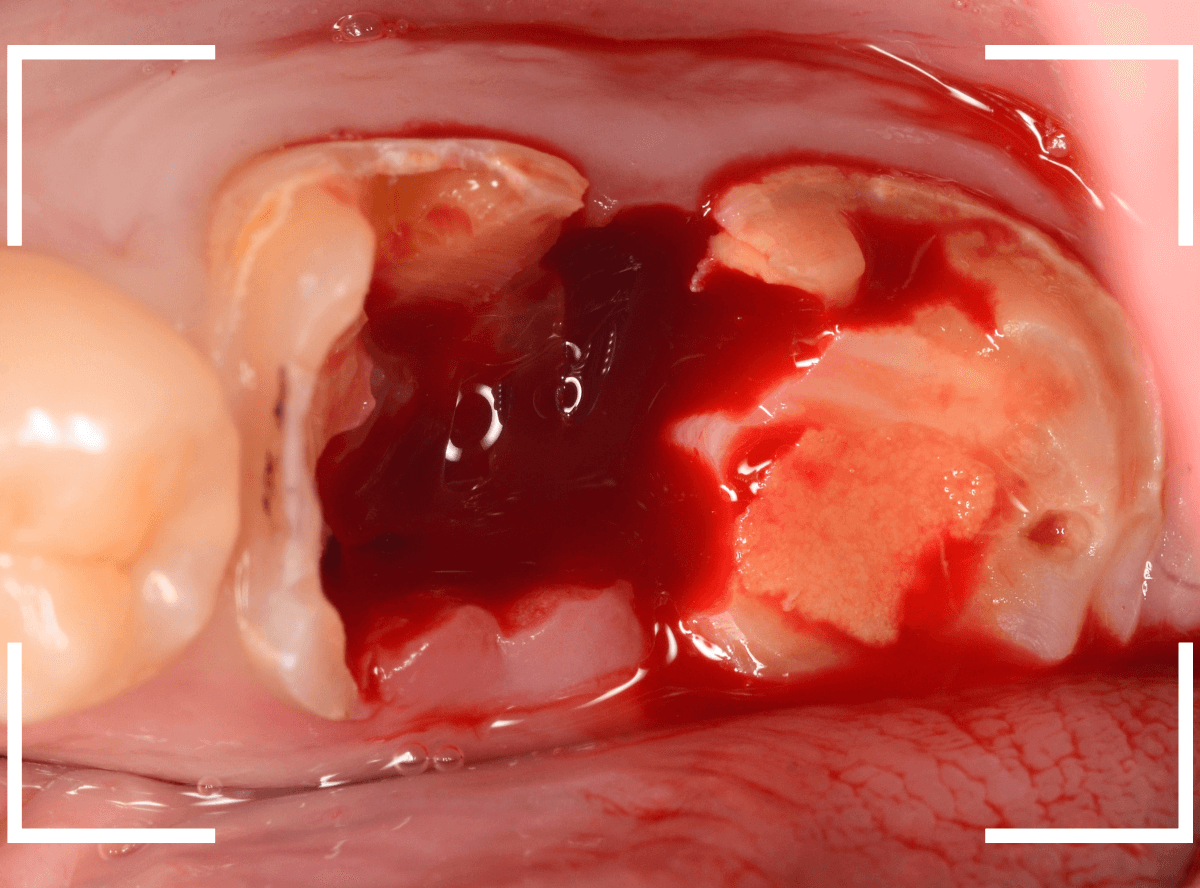

Case.15 歯肉の中まで、虫歯が進行

今回は、下の奥歯が虫歯になってしまった方です。

銀歯の下が大きくかけていますが、神経を取っている歯なので痛みはありません。

隣りの奥歯は、土台のまま治療途中になっています。

レントゲン写真で確認します。

赤い部分が虫歯、青い線が歯肉のラインです。

奥歯2本とも虫歯になっています。

どちらも虫歯が深く、歯肉の中まで入り込んでいると思われます。

この虫歯の深さは、最悪、抜歯が必要になるかもしれないケースです。

神経のない歯ですが、歯肉を処置する必要があるため、麻酔をして治療します。

まず、つめものを外します。

歯肉を処置しながら、虫歯を除去します。

虫歯の全て除去後、止血したところです。

かなり深いところまで虫歯が進行していましたが、なんとかぎりぎり抜歯せずに、土台を作って噛み合わせを回復できそうです。

神経を取った歯は、虫歯がいくら進行しても痛みにならず、最悪、抜歯一直線になってしまいます。